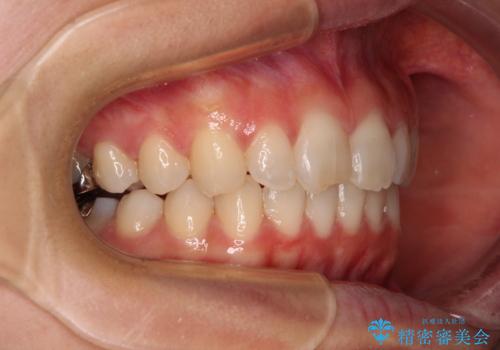

- 近々転勤の予定があるが、早めにインビザラインによる矯正治療を始めたいとのことで来院された患者様です。

上下ともにデコボコの程度は著しいものではなく、インビザラインで十分に対応可能な歯列不正でした。

後戻りによりスペースができてしまうことを避ける目的で、IPR(歯と歯の間を削る)を極力用いない矯正治療を行うこととしました。